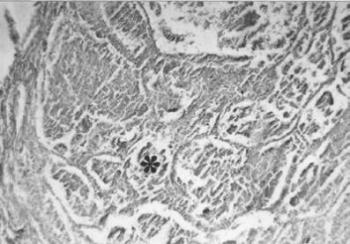

Az arteriosclerosis következményei